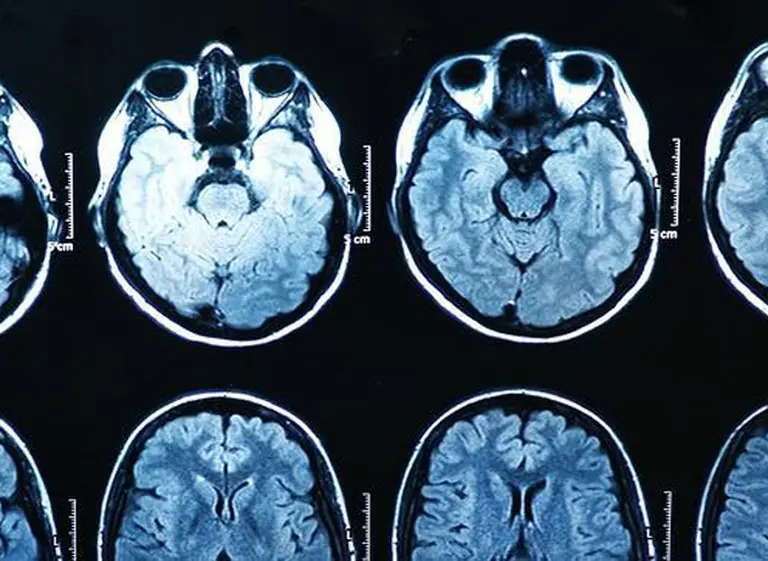

En la investigación, realizada por científicos del Instituto Max Planck de Berlín, los científicos analizaron la actividad cerebral de 64 hombres y la compararon con sus hábitos de consumo de pornografía. Y como resultado, descubrieron entre otras cosas que las personas qué pasaban más tiempo viendo porno tendían a tener un cuerpo estriado, una zona del cerebro relacionada con el placer y los circuitos de recompensa, más pequeño. Pero, ¿qué importancia tiene este cuerpo estriado? ¿Qué implica que sea más pequeña?

"Es una región muy bien conocida, muy importante para actividades relacionadas con recompensas", explica José Antonio Esteban García, un neurobiólogo del Centro de Biología Molecular Severo Ochoa de Madrid que trabaja en averiguar cómo funcionan en el cerebro los procesos relacionados con el aprendizaje y la memoria al nivel de las células. El cuerpo estriado "interviene en respuestas relacionadas con el placer, como el que se produce al comer o tener sexo, o con el consumo de drogas", aseguró el especialista al diario ABC de España.

Y según explica, el hecho de que esta región se haga más pequeña no es necesariamente negativo: "Cuando una estructura cambia de tamaño no significa que no funcione o que esté atrofiada. Cuanto mejores nos volvemos en realizar una tarea concreta, en general necesitamos menos activación del cerebro, porque se refuerzan conexiones útiles entre neuronas y te basta con ellas".

Teniendo en cuenta todo esto -concluye el artículo- parece razonable que los hombres que tienden a usar con frecuencia unas regiones del cerebro asociadas con la recompensa y el placer sexual, sufran algunos cambios gracias a la plasticidad sináptica. Y por ello no es descabellado que su cuerpo estriado cambie y sea más pequeño, ya que participa en estos procesos.